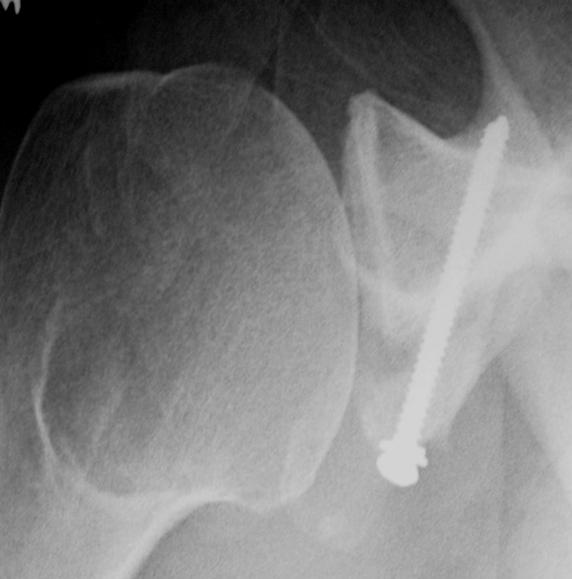

From www.arthroscopytechniques.org

Arthroscopic Acute Bony Bankart Repair in Lateral Decubitus What Is Shoulder Bankart Repair Surgery for a bankart lesion involves removing dead or damaged tissue and repairing the tear in the. bankart lesions usually report a primary or recurrent anterior shoulder dislocation. a bankart lesion repair is usually carried out arthroscopically (hey hole surgery) under general anaesthetic. The labral tear surgery aims to repair. Minimally invasive surgical procedure to repair a tear. What Is Shoulder Bankart Repair.